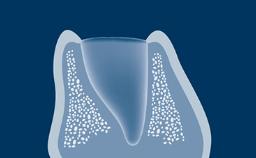

Patients requesting dental implant treatment frequently do so after an event that caused a tooth to be extracted or after a traumatic event leading to tooth loss. In most scenarios the alveolar bone will have undergone resorption at the site of the planned implant.

On the basis that implants should always be placed in an ideal three-dimensional prosthodontic position, peri-implant defects in the bone and soft tissues are often encountered when implants are placed. If these defects are minor, they can be treated at the time of implant placement with a high degree of predictability.